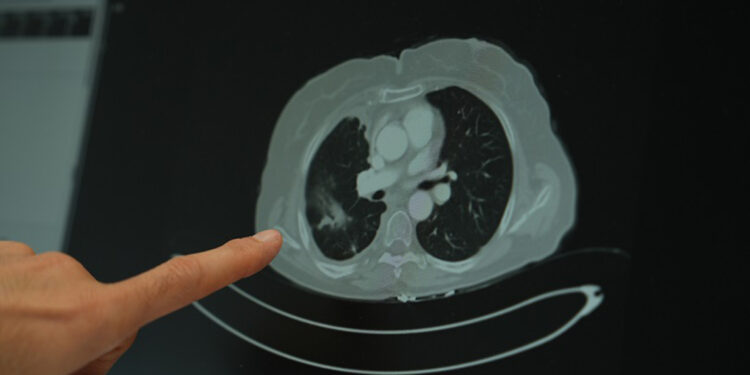

Ailesinde kanser öyküsü bulunan gençlerin çok daha dikkatli olması gerektiğini vurgulayan Doç. Dr. Şimşek, “Ailede kanser varsa, tarama yaşları çok daha genç yaşlara çekilebiliyor. Bazı durumlarda 18-20 yaşlarından itibaren düzenli kontrollerin yapılması hayati önem taşıyor” diye konuştu. Sigara kullanımının akciğer kanseri üzerindeki etkisini değerlendiren Doç. Dr. Şimşek, uzun süre sigara kullanan kişilerde düşük doz radyasyonla yapılan tomografi taramalarının önerildiğini belirterek “Sigara içen bireylerde akciğer kanseri riski yüksek. Bu nedenle düşük doz radyasyonlu taramalar, erken tanı açısından önemli” ifadelerini kullandı.